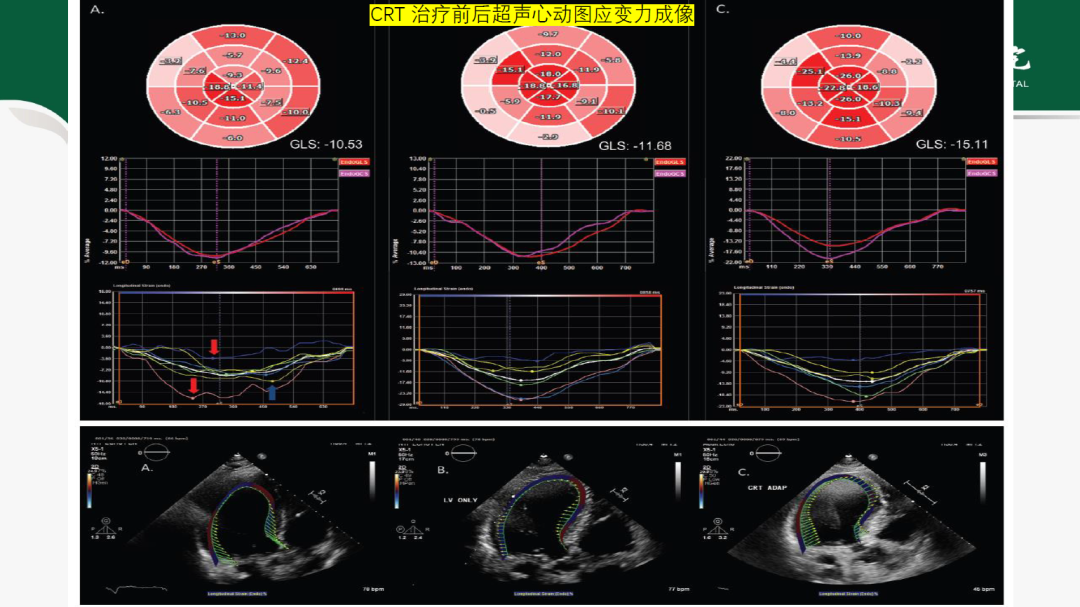

本期由褚华清医生与宋锴澄博士为大家解读《Miller麻醉学》(第九版)第38章植入式心脏起搏装置。

随着社会老龄化加快和预期寿命的延长,临床上常见安装了植入式心脏起搏装置的患者接受其他手术的情况。作为麻醉医师,需要掌握植入式心脏起搏装置的类型、工作原理、适应证和围术期注意事项,以在麻醉过程中能对突发情况进行处理并确保患者安全。